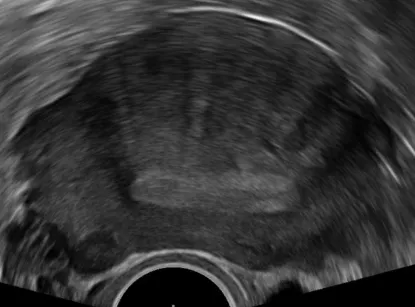

- 📊 Transvaginal USS: First-line structural imaging

Imaging Decision Points:

- 🚩 Always USS if: Palpable pelvic mass, examination difficult/abnormal, pharmaceutical treatment failed